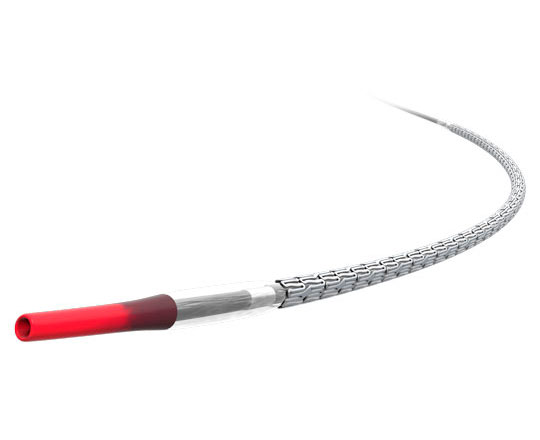

Tiene un esqueleto de nitinol con dos filas de 20 anclajes que se fijan a la pared de la orejuela, con un recubrimiento matricial de espuma en forma de tapón. En la parte superior de este, la expuesta al contacto sanguíneo, lleva un recubrimiento con tejido de politetrafluoroetileno expandido (ePTFE) que evita la trombosis del dispositivo1.

La matriz de espuma permite sellar con mayor eficacia posibles fugas de otros dispositivos, y se adapta a la mayor parte de anatomías de la orejuela con solo dos tamaños. La gran ventaja del recubrimiento de ePTFE es que reduce de manera importante la formación de trombos sobre el dispositivo, sobre todo cuando la anticoagulación o la antiagregación están contraindicadas.